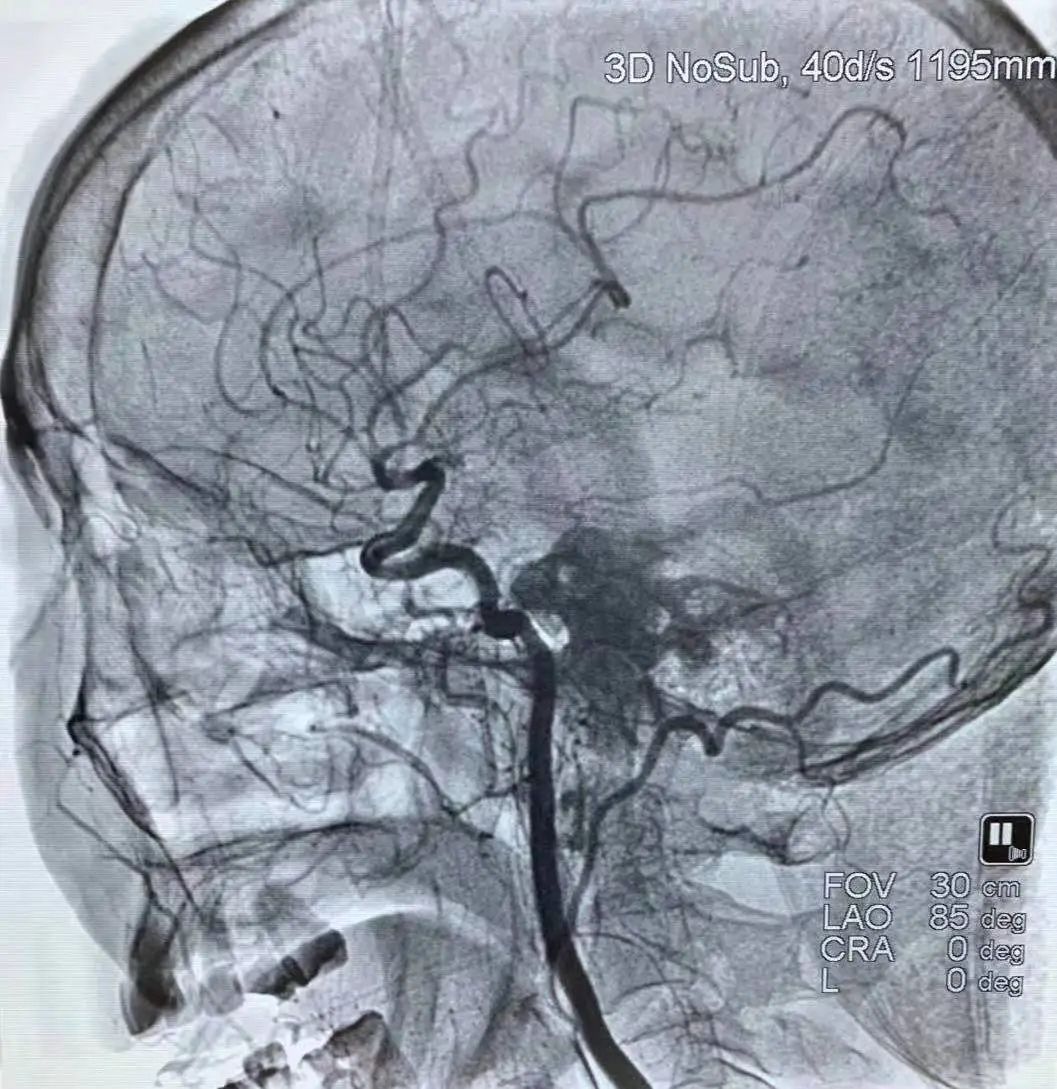

血管内的治疗还包括血管狭窄的治疗,在做头颅磁共振或脑血管造影时,如果发现有血管狭窄,医生就会建议放一个支架,这样就避免了脑梗塞的发生。

近年来,脑血管介入治疗显著提高了闭塞血管的开通率,为静脉溶栓失败和溶栓禁忌的大动脉闭塞患者提供了一种新的治疗选择。但具体诊疗过程中还要因病施治,要根据病人的病情决定什么样的治疗。